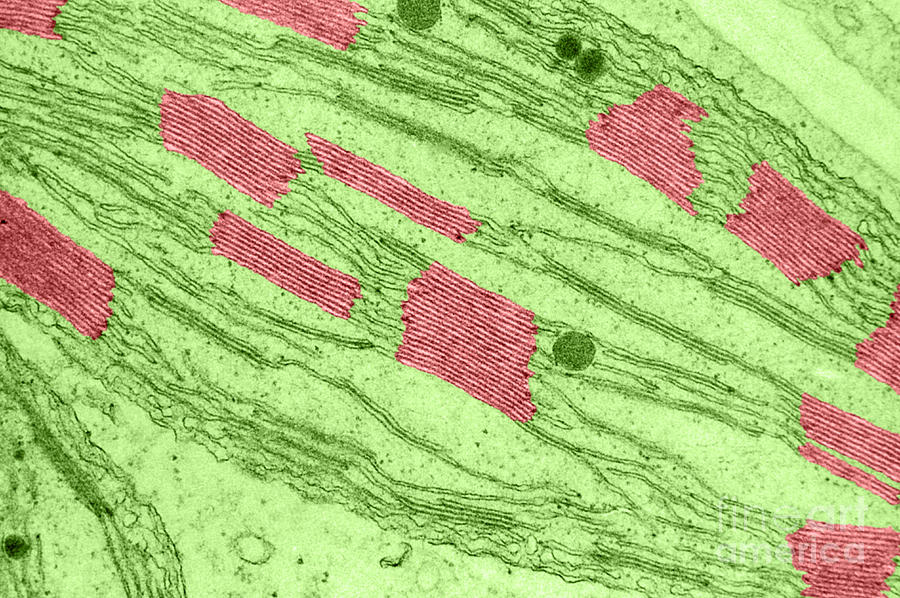

Left-side: Fluo-4 showing an induced Calcium signal, Right-side: Di-8-ANEPPS labeling the sarcolemma

Using 100X objective at 330fps capture speed, exposures at 2ms and streamed in a 200 frames